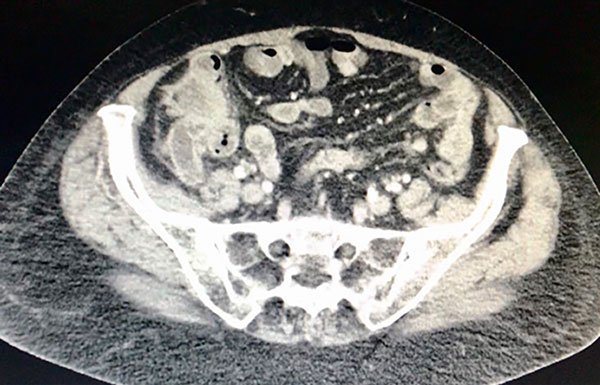

La TAC del abdomen y pelvis muestra engrosamiento parietal circunferencial e irregular del ciego. Se asocia a cambios sutiles en la densidad de los planos grasos adyacentes, ingurgitación de los vasos sanguíneos regionales y dos adenomegalias con centro hipodenso atribuible a necrosis en el territorio ileocólico, la mayor de 13 mm (Figs. 2 y 3).

Figura 2: TAC del abdomen que evidencia engrosamiento cecal y apendicular con compromiso ganglionar local.